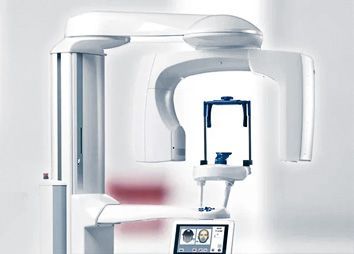

Наше оборудование